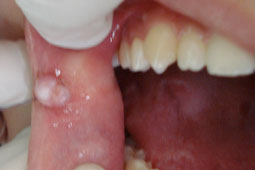

L’examen des muqueuses révèle la présence d’un nodule sessile de 10 millimètres de diamètre, de consistance ferme, indolore, souple. La muqueuse de recouvrement est d’aspect normal avec au sommet une plage kératosique. (Fig.1).

• Une exérèse chirurgicale de la totalité de la lésion (fig.2, 3 et 4).